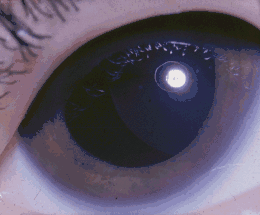

| A six-year-old girl with Weill-Marchesani syndrome, which has caused a dislocated lens. | |

The eye manifestations typically include unusually small, round lenses of the eyes (microspherophakia), which may be prone to dislocating (ectopia lentis), as well as other ocular defects. Due to such abnormalities, affected individuals may have varying degrees of visual impairment, ranging from nearsightedness myopia to blindness. Weill–Marchesani syndrome may have autosomal recessive inheritance involving the ADAMTS10 gene, or autosomal dominant inheritance involving the FBN1 gene.[1] In some cases there is no association with either of these genes.[1]